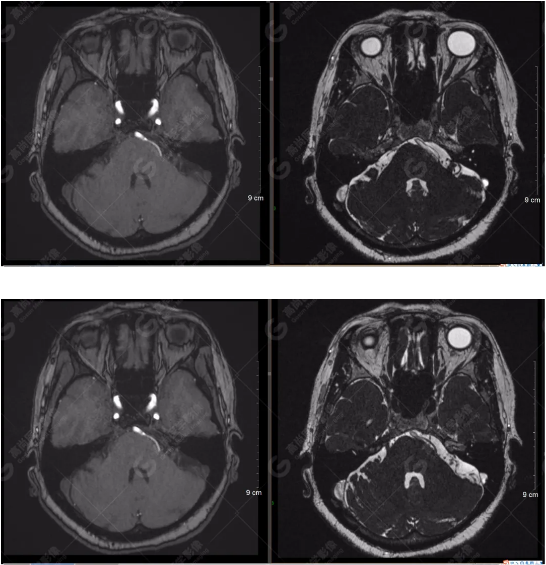

檢查圖像

顱腦MRA及ciss序列示腦基底動(dòng)脈環(huán)完整,雙側(cè)頸內(nèi)動(dòng)脈末段、大腦前動(dòng)脈、大腦中動(dòng)脈、大腦后動(dòng)脈及其主要分支顯影良好,管徑及走行正常,無明顯局灶性增粗或變細(xì)。雙側(cè)椎動(dòng)脈末段沿延髓左側(cè)向上走行,左側(cè)面聽神經(jīng)輕度受壓移位,左側(cè)面聽神經(jīng)周圍見細(xì)小血管包繞。右側(cè)面聽神經(jīng)及雙側(cè)三叉神經(jīng)周圍未見異常血管影。

1.雙側(cè)椎動(dòng)脈末段沿延髓左側(cè)向上走行,左側(cè)面聽神經(jīng)輕度受壓移位,左側(cè)面聽神經(jīng)周圍見細(xì)小血管包繞,可符合面聽神經(jīng)壓迫綜合征。